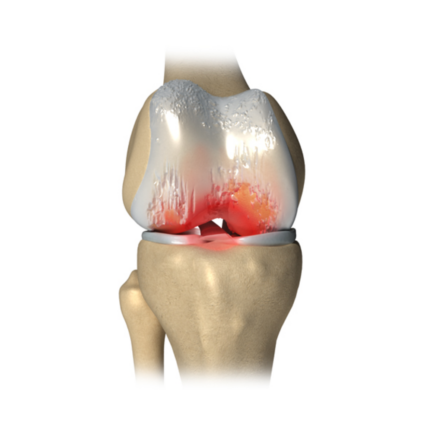

Knee Arthritis

Knee Preservation